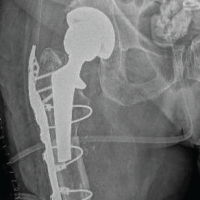

A computed tomography (CT) scan revealed dislocation and fracture at the lateral facet of the patella (Fig. 4). The placement of the TKA components was checked and found to be correct, so we focused on the instability of the extensor mechanism and the soft-tissue imbalance.

Evaluating the proper placement of the arthroplasty components, the patellar fracture, the reduced anteroposterior diameter of the patella, the loose medial retinaculum, and the patient’s history of osteopenia, we decided on surgical management with proximal realignment of the extensor mechanism according to Insall procedure, as it is described in his book, complemented by a lateral release. We started with a midline incision supra and infrapatellar, approximately 10 cm long, following the previous scar. We continued with a medial parapatellar approach from the quadriceps tendon, leaving about 2 mm of the vastus medialis for suturing, down medially to the patellar ligament. We then proceeded with the eversion of the patella and located the fragment of the lateral facet, which was excised and found to be approximately 20% of the patella. Next, we performed a lateral release and advanced the vastus medialis distally and laterally in line with his oblique portion, overlapping about half of the upper pole of the patella (Fig. 5), and sutured the vastus medialis in this position. We checked the centering of the patella in the trochlea groove throughout the full range of knee motion and found it to be satisfactory (Fig. 6). After that, the incision underwent a rich lavage and was closed.

In general, the risk factors for patellofemoral joint instability after total knee replacement can be categorized into three groups, component positioning and surgical technique, soft-tissue balancing, and other causes [1,2,3,6]. In our patient, the femoral and tibial components were found to be correctly placed on the CT scan. The patient had a mild valgus knee joint alignment of approximately 10°. As described in the literature, valgus knees are predisposed to patellar instability [2,7]. In cases of valgus deformity, the posterior cruciate ligament is often contracted, making it more difficult for the surgeon to correct the deformity.[8] In addition, posterior-stabilized components tend to be more stable and can be more lateralized to improve patellar tracking in the trochlear groove [9,10,11]. This is why we decided to use a posterior-stabilized total knee replacement in our patient, along with the fact that the medial retinaculum appeared very thin. There is also a greater risk of soft-tissue imbalance in patients who undergo a medial parapatellar approach [1,12]. We believe that in our patient, the main factors contributing to secondary post-operative patellar subluxation were the valgus malalignment, which led to chronic imbalance with a fragile medial retinaculum and chronic impingement of the lateral facet of the patella where the bony prominence was found. Due to the thinned and fractured patella, we chose not to reconstruct the medial patellofemoral ligament, even though excellent results are reported in the literature [1,13]. We also avoided distal realignment due to the risk of material failure, nonunion, patellar tendon rupture, and osteonecrosis of the fragment, especially after a cemented TKA in an osteopenic patient [1,2]. Hence, we proceeded with proximal realignment using the Insall procedure [1], which appeared to be safer [2] for the patient, along with a lateral retinaculum release. In addition, due to the removal of the fractured lateral facet, we performed a lateral facectomy, which in combination seem to have good results for patellar instability after TKA [1,12].